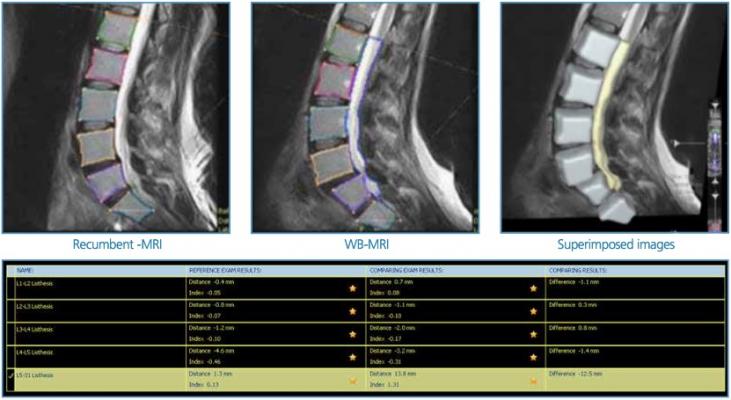

Q-Spine facilitates and simplifies the analysis of weight-bearing versus recumbent MRI through semi-automatic segmentation of the Lumbar-spine. The system provides a numerical quantification of the relative changes, establishing reliable and coherent measures by taking out the “human factor.” It provides the ability to evaluate patient follow-up with numerical evidence, and generates a PDF report to be attached to the medical report

Guyer stated, “We are excited to present the Q-Spine software, which is a semi-automated software analysis used with the Esaote weight-bearing Brio G MRI scanner, which reliably calculates spinal canal area, dural diameter, lumbar lordosis and sacral angles. We believe this will demonstrate nerve compression which may not be diagnosed with supine MRI scanners and help surgeons manage sagittal alignment in their patients.”